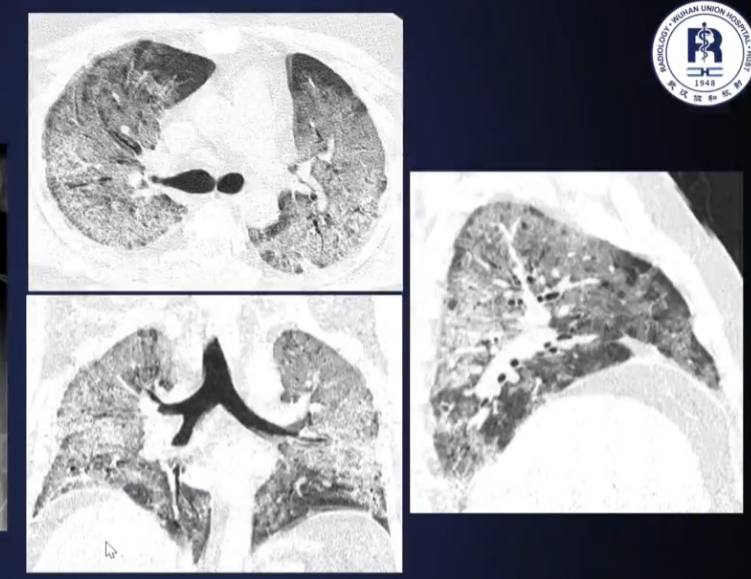

- 重症:双肺弥漫性浸润,实变+磨玻璃影,少量胸水等

重型表现

与AI结合

- 量化评估:根据分割得到感染区域大小、百分比

- 三维可视化